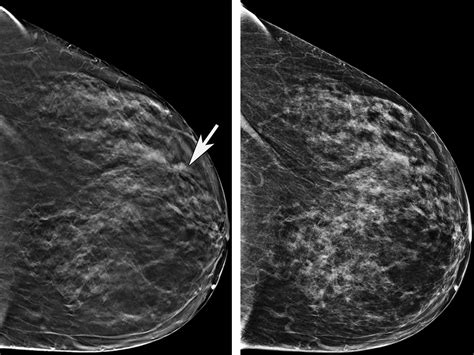

• 3D Mammography (Tomosynthesis): This technique takes multiple images from different angles and reconstructs them into a 3D image, providing a more detailed view of the breast tissue.

• Breast Tissue Density: Dense breast tissue can obscure small abnormalities, making them more difficult to detect.

• Overlapping Tissue: Overlapping breast tissue can create the appearance of abnormalities, leading to false positives.

Radiologists must be highly trained and experienced to accurately interpret mammogram images and distinguish between normal and abnormal findings. They use a combination of visual inspection, pattern recognition, and advanced imaging techniques to ensure accurate diagnosis.